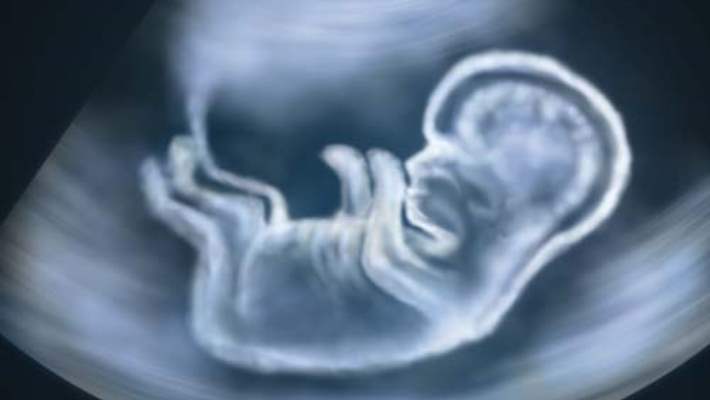

Durum hamile anneye anlatılabilir. Ancak bu yöntemin başarısını yüzde yüz olarak görmemek gerekir. Çünkü bazen sorun gözden kaçabilmekte ya da atlanabilmektedir. Yani hamile anneye yapılacak bir ekokardiyografi ile bir kalp sorununun olduğu yüzde yüz anlaşılacak diye bir şey yoktur. Bazı anomaliler hamileliğin son dönemine doğru belirginleşebilir. Bu nedenle fetal ekokardiyografi, hamile annelerin bir ya da iki defa yaptırabileceği bir test olarak ele alınmalıdır.